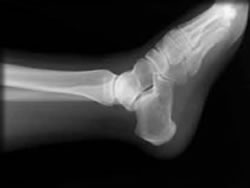

右腕擦り傷治療の後、日曜日なので緊急内科医が左足首と右肋骨レントゲン撮影、検査結果、「骨には異常ないが左足首の靭帯切断の恐れあり」とのことで、明日の専門の先生に診察を託し、応急ギブスをセットし、松葉つえで帰宅しました。

左足首の腫れが著しく、再度レントゲン撮影のところ、「距骨剥離骨折と靭帯損傷切断」と判明。

午後、整形外科手術のため断層及び造影写真、さらに靭帯連結程度を調べる関節曲げ試験(これが痛い)、その結果、関節内出血、距骨骨折と内側靭帯切断、外側靭帯は辛うじて繋がっていて全切断を免れました。

こちらが下半身

(本人出演)

あらららら・・!